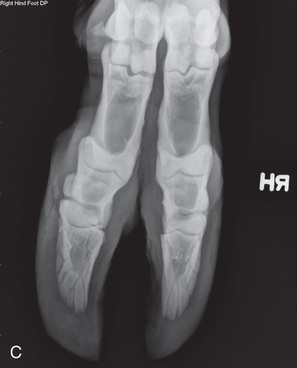

Equipment requirements and positioning techniques for bovine radiography are the same as those for equine radiography. Handling restrictions may hinder the options and available positions. See Table 24.4 for the common views.

Digit/foot: P-III (distal phalanx, coffin bone) P-II (middle phalanx) P-I (proximal phalanx-pastern) Proximal interphalangeal joint (pastern joint) joint | DP (Standard) (Fig. 24.62B,C) | Dorsal 45-degree proximal–palmarodistal (D45Pr-PaDi) | Foot slightly forward on image receptor. | Perpendicular to foot axis at MSP (midsagittal plane) at area of interest with beam angled ~45 degrees to ground |

| Lateral (Standard) (Fig. 24.62D) | Lateromedial | On a block to elevate limb for P-III; resting on ground for other views. | 90 degrees lateral to MSP, parallel to ground on area of interest: coronary band for PIII | |

bFurther specifications with preparation and positioning for the digit: Before a digit radiograph is taken in the bovine patient, the interdigital space and both claws should be cleansed thoroughly and lightly trimmed. If this step is not taken, false images or shadows may mask abnormalities present in the claws. The digits can be viewed radiographically using four angles or projections.6